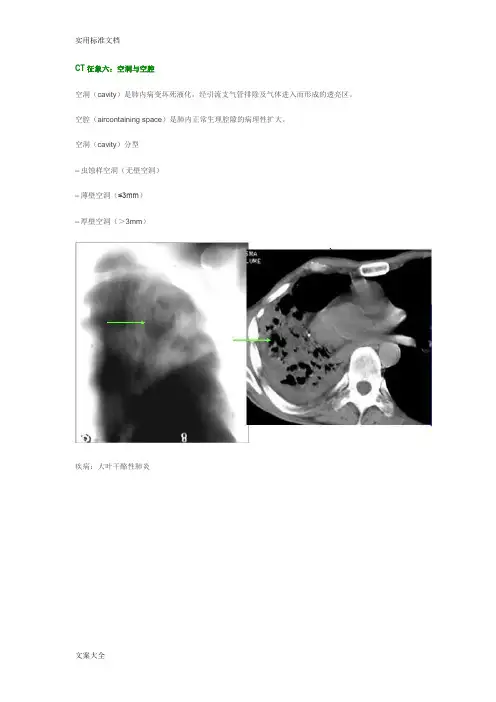

CT征象六:空洞与空腔空洞(cavity)是肺内病变坏死液化,经引流支气管排除及气体进入而形成的透亮区。

空腔(aircontaining space)是肺内正常生理腔隙的病理性扩大。

空洞(cavity)分型–虫蚀样空洞(无壁空洞)–薄壁空洞(≤3mm)–厚壁空洞(>3mm)疾病:大叶干酪性肺炎疾病:继发型肺结核结核球厚壁空洞肺脓肿厚壁空洞肺鳞癌厚壁空洞空腔病变CT征象七:马赛克灌注马赛克灌注(Mosaicperfusion)——在HRCT上,由于气道疾病或肺血管性疾病引起相邻的肺区血液灌注上的差别而出现的不均匀肺密度区,称马赛克/镶嵌性灌注。